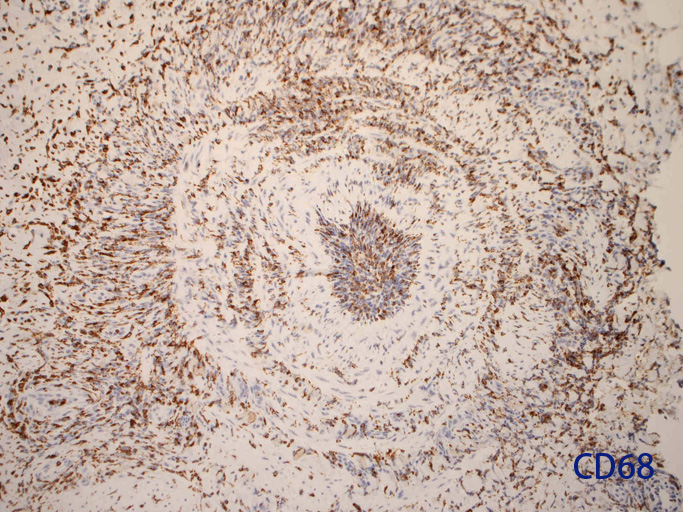

免疫染色:血管腔を閉塞する細胞の多くはCD68, CD163陽性細胞. CD34陽性内皮が保たれている。

CD68lpf.jpg

CD68hpf.jpg

CD163.jpg

CD34.jpg

CD68CD68CD163CD34